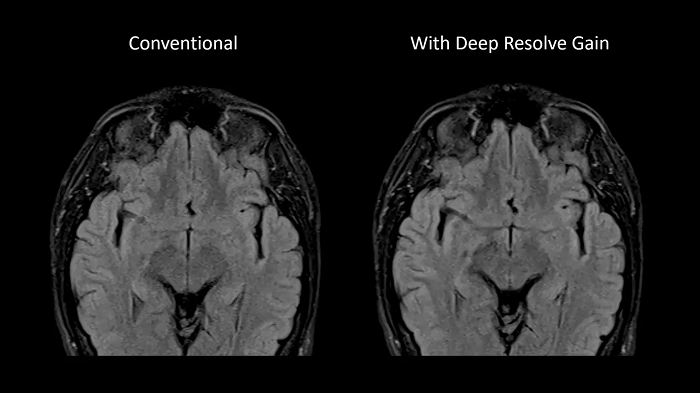

Deep Resolve Gain

Deep Resolve Gain, a constructive technique, utilizes individual quantitative noise maps in the reconstruction process for targeted denoising. It increases image quality to ensure the best diagnostic abilities and is available for a wide range of sequences.

Image Courtesy: University Hospital Erlangen, Germany | Image-ID: 4aaaa0297